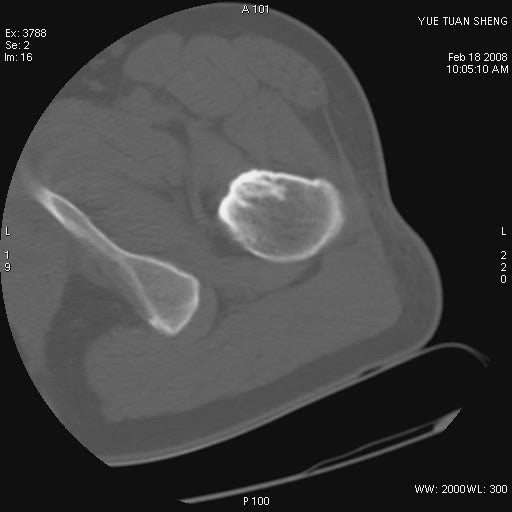

患者,男,56岁,左髋部疼痛1个月,x线:左股骨头高密度影,性质待定,右侧正常。左髋ct如图

左股骨颈区椭圆形磨玻璃样影,边缘明显硬化环环绕,其内见斑点状类钙化高密度影考虑 良性骨病-----骨纤,骨化性纤维瘤,内生软骨瘤。